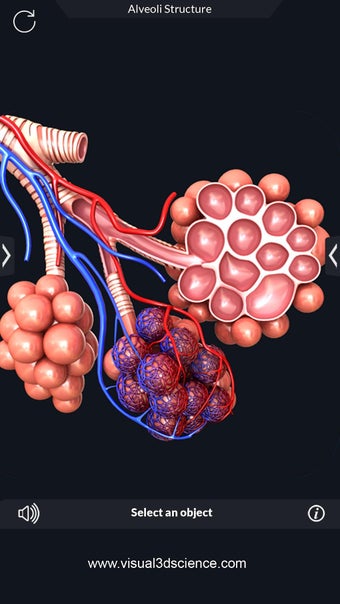

Una aplicación gratuita para Android, creada por Visual 3D Science.

La anatomía humana es una aplicación educativa médica que te permite explorar el cuerpo humano desde todos los ángulos. Ofrece una mirada detallada a la anatomía de los diferentes sistemas, así como a los órganos y sus funciones. Es una referencia perfecta para estudiantes y profesores de medicina.

Puedes seleccionar cada parte del cuerpo por separado para ver su nombre o leer información relacionada. Puedes ocultar y mostrar cada parte del cuerpo, así como rotar 360° alrededor de un modelo 3D altamente realista. Puedes dibujar en la pantalla o compartir capturas de pantalla con tus amigos. Puedes encontrar la definición de cada parte del cuerpo y su anatomía.